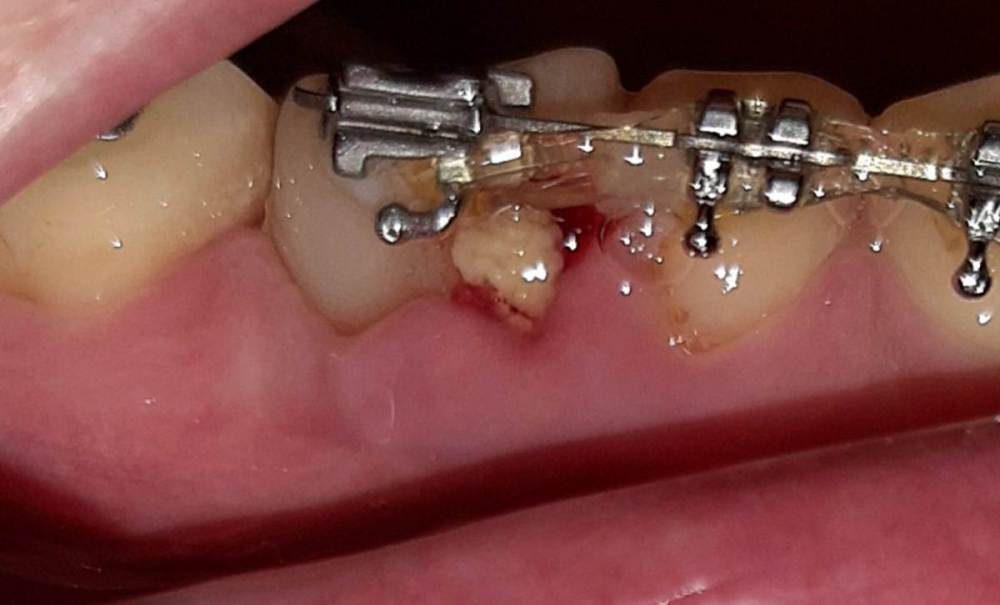

Выход костного материала через 1 год и 3 месяца после наращивания костной ткани

Здравствуйте, возможен ли выход костного материала наружу  через 1 год и 3 месяца после имплантации? Если возможен, то в чем причина? И второй вопрос  - где должна быть коронка, где красные линии, или где желтые, и что это на снимке - отмечено зеленым?